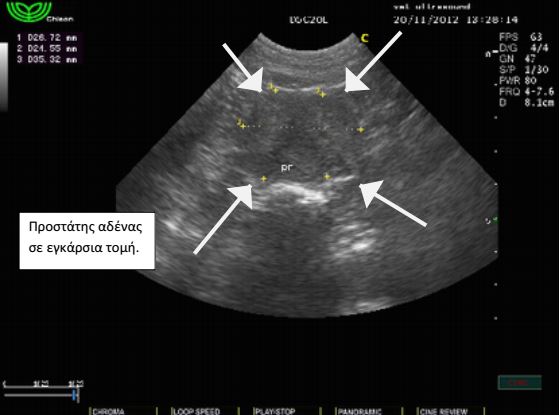

Σε γενική εξέταση αίματος κατά τον ετήσιο προληπτικό έλεγχο βρέθηκε ήπια μείωση του αιματοκρίτη και μέτρια αύξηση των λευκών αιμοσφαιρίων.Έγινε υπέρηχος κοιλίας όπου και διαπιστώθηκε ήπια διόγκωση του προστάτη αδένα. Τα υποσφυικά λεμφογάγγλια δεν βρέθηκαν διογκωμένα. Τα υπόλοιπα όργανα ήταν εντός των φυσιολογικών ορίων και χωρίς απώλεια της φυσιολογικής δομής τους. Στο παρέγχυμα των όρχεων εντοπίστηκαν αλλοιώσεις σαφώς περιγεγραμμένες με υποηχογενή άλω. Το FNB( fineneedlebiopsy) των αλλοιώσεων αποκάλυψε πως πρόκειται για μια νεοπλασματική εξεργασία των όρχεων, το σερτολίωμα. Οι αλλοιώσεις αυτές παράγουν οιστρογόνα και για το λόγο αυτό, μακροπρόθεσμα, μπορούν να προκαλέσουν απλασία του μυελού των οστών και μείωση του αιματοκρίτη. Το περιστατικό αντιμετωπίστηκε με ορχεκτομή. Μετά από λίγους μήνες οι αλλοιώσεις του προστάτη υποχώρησαν και η τιμή του αιματοκρίτη αποκαταστάθηκε στα φυσιολογικά επίπεδα